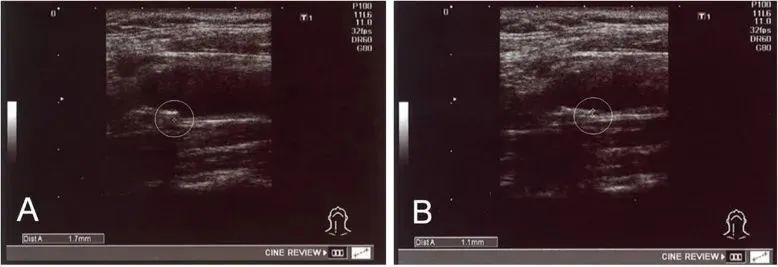

在《Stem Cell Res Ther》发表的一篇文章中,研究者收集了78名使用自体干细胞治疗动脉硬化的患者数据,包括他们给药前后的脂质分布、内膜中膜厚度 (IMT)等。

研究者对这些数据对比后发现:

①、12名在治疗前高密度脂蛋白值异常 (≤ 40 mg/dL) 患者,有 11 名 (91.7%) 在治疗后改善;

②、18例IMT值异常(≥1.1 mm)的患者,在治疗后IMT值均显著减少;

③、28例残余样颗粒胆固醇水平异常患者里,有24例得到改善(85.7%)

④、10名临界动脉硬化疾病的患者在接受干细胞治疗后得到改善,例如低密度脂蛋白降低和甘油三酯水平降低。

经过治疗,实验中一名患者 IMT 从 1.7 毫米降至 1.1 毫米

实验证实:干细胞可以改善血清中的高密度脂蛋白,低密度脂蛋白和残余样颗粒胆固醇水平,调节脂质代谢,能够安全有效地改善动脉粥样硬化。